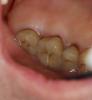

Doc Опубликовано 31 октября, 2008 Поделиться Опубликовано 31 октября, 2008 последний абзац о том, что Док поспешил и не проверил наличия ценных данных вне жесткого диска компа..... И снёс все эти ценные данные нафих... Ну да. Спасибо, что у меня на буке оказалась эта папка, в которой процентов 80, а то и все 90 снимков и лекций сохранились. А все, что было в последние два-три месяца - пропало нафих и дальше, чем нафих.... ((( Вот еще случай гемисекции смешной. У пациента сахарный диабет сильный, потому противопоказание к имплантации, синусу, подсадке кости и всему прочему. А два щечных канала у семерки были убиты насмерть. И тогда пришлось делать то, чего нормальные люди не делают в жизни, гемисекцию, только гемисекция это разделение зуба на половину, а тут отделение от зуба двух третей вышло. Один небный канал оставили. Правда снимков во рту нет теперь, пропали, зато есть снимки модели и самого мостика, а так же мостика на модели. А вот это контрольные снимки через год. Кажется авантюра удалась. Синюшная слизистая немного, но это нормально для него. При его диабете у него на других коронках во много раз хуже десна. И это еще золото, был бы КХС было бы еще хуже. Ссылка на комментарий